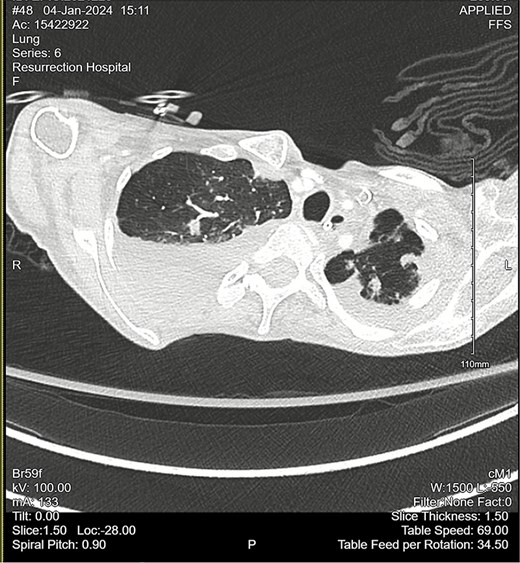

Computed tomography (CT) angiogram of the chest demonstrated numerous small nodular and patchy opacities throughout the upper lobes ranging from punctate to 1.2 cm in diameter (Figs 1 and 2). Additionally, bilateral pleural effusions with extensive atelectasis were also observed.

CT chest angiogram with a coronal cross section. Bilateral pleural effusions with atelectasis are observed. Ground-glass opacities with scattered nodules are present in the upper lobes. Lung volumes are reduced. There are no signs of embolism in pulmonary arterial segments.